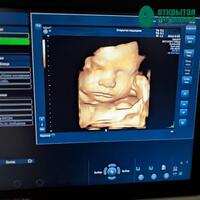

УЗИ 3D и 4D отличается от обычного тем, что позволяет видеть малыша более объемно и детально. Благодаря этому получаем возможность увидеть лицо ребенка, его черты, мимику и движения.

Для родителей акушерское УЗИ – возможность увидеть своего кроху. Многие мамы и папы с огромным волнением ждут этого момента!